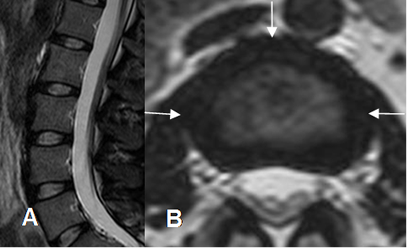

En RM el núcleo pulposo hidratado es hiperintenso en T2 y el anillo fibroso hipointenso.

En personas mayores de 30 años puede encontrarse una banda fibrosa, hipointensa en T2 a nivel del núcleo pulposo, que corresponde a la hendidura intranuclear. (5). (Fig 17 y 18).

Fig 17. Disco normal en RM.

A: RM sagital y B: RM axial en T2. Discos intervertebrales normales, con el núcleo pulposo hiperintenso y el anillo fibroso hipointenso.

Fig 18. Hendidura intranuclear.

RM sagital en T2. Zona hipointensa central en el núcleo pulposo, que corresponde a la hendidura intranuclear central.